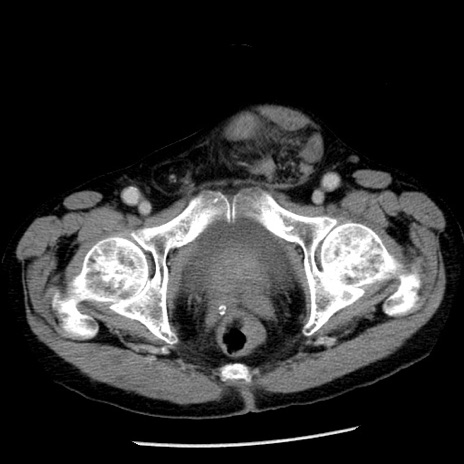

症例26(横断像)

【症例】80歳代男性

【主訴】嘔吐

【現病歴】昨晩2回嘔吐あり、今朝になっても嘔吐あり。来院。

【既往歴】胃潰瘍

【身体所見】意識清明、BT 37.6℃、BP 166/95mmHg、HR 100bpm、SpO2 97%、腹部:平坦・軟、腸蠕動音聴取良好、圧痛なし。

【データ】WBC 21900、CRP 1.46